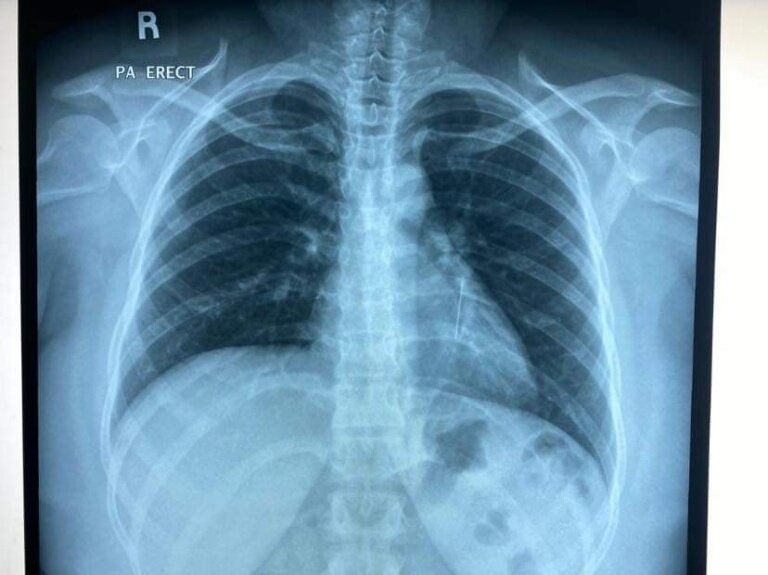

"Semalam tim Respiratory UKMMC keluarkan sebatang jarum pentul dari paru-paru kiri seorang wanita melalui prosedur rigid bronchoscopy. Ngeri!," tulisnya.